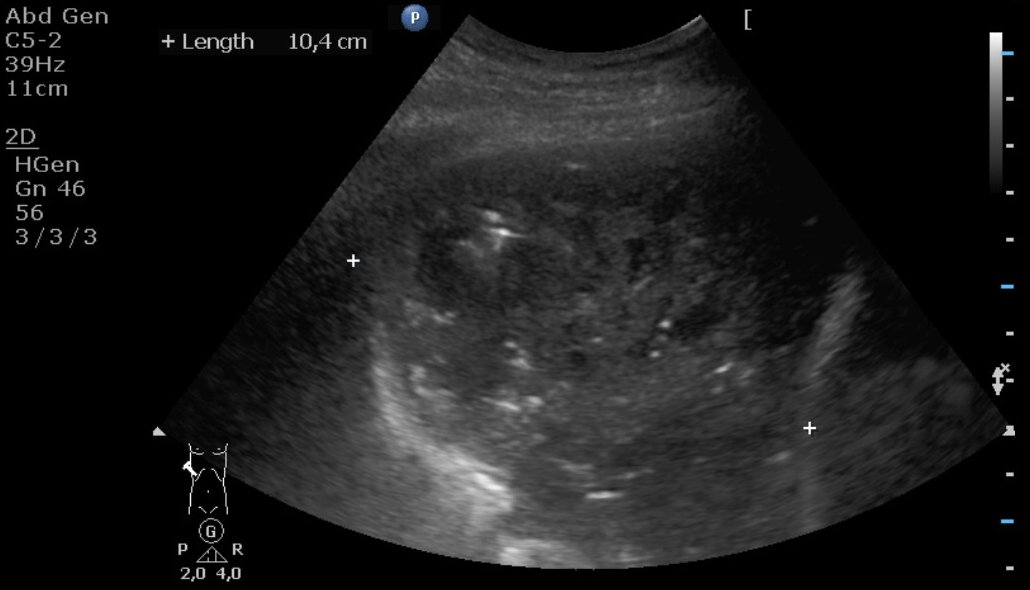

Image

6. g

g.). US: The lung parenchyma has an inhomogenous pattern on the right side above the diaphragm measuring 10 cm in wideness, without air content. It includes hypoechoic areas of irregular contours measuring 18-39 mm in diameter including tiny „bright” gas bubbles.